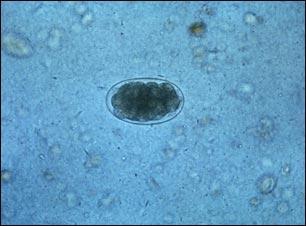

Huevo de anquilostoma

Este es un huevo de anquilostoma. Los anquilostomas eclosionan en la vegetación húmeda y sus larvas pueden penetrar el cuerpo humano a través de la piel, incluso cuando ésta no presenta cortaduras ni abrasiones. Una vez que atraviesan la piel, comienzan el siguiente paso de su ciclo vital.